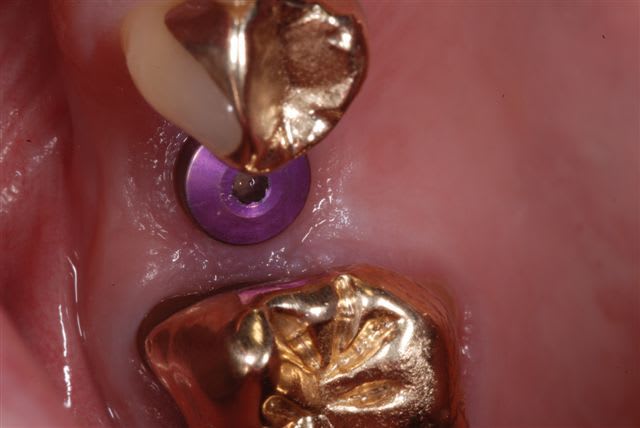

comparaison photos prises avec flash Metz 15 et sigma 140 DG, même boitier (Nikon D80) iso 100, f32, i-ttl, mise au point manuelle.

bon alors pour faire comme suggéré par D57:

(f16, iso 100, même cadrage, boitier et rapport d'agrandissement, i-ttl)

voilà typiquement la différence obtenue entre ces deux flashs